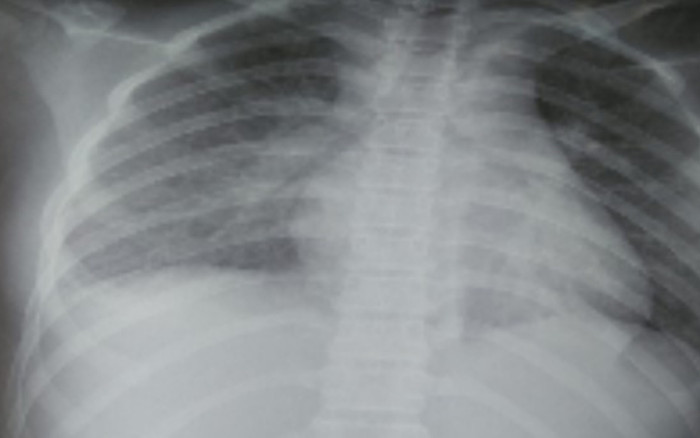

Hình ảnh X-quang cho thấy tổn thương ở phổi. (Ảnh: Sức Khỏe & Đời Sống).

Kết quả các xét nghiệm cho thấy tổn thương nhiều cơ quan, trong đó phổi có tổn thương mờ dạng kẽ vùng rốn phổi 2 bên; tim có tràn dịch màng ngoài tim; tăng chỉ số Troponin T, pro-BNP. Các chỉ số men gan ASAT/ALAT cũng tăng gấp 2 lần. Các chỉ số viêm tăng rất cao, định lượng Interleukin-6 (cytokine viêm) cũng tăng cao.